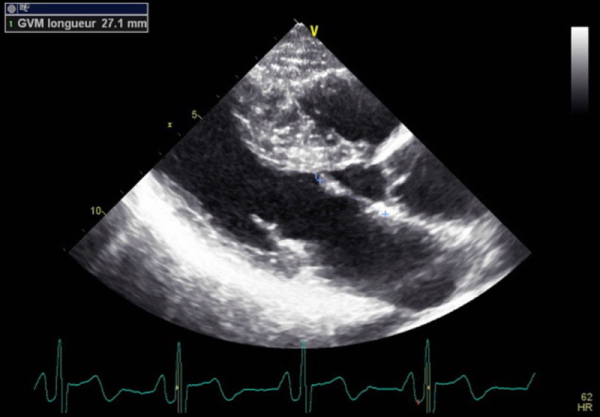

L’échocardiographie d’effort est l’examen de choix qui permet d’évaluer le patient porteur de CMH, à la fois sur le plan fonctionnel, tout en permettant d’objectiver une obstruction absente à l’échocardiographie de repos (latente)(Figure 1) et son mécanisme (Figure 2). Si la prévalence de l’obstruction de repos est de l’ordre de 25 % à 40 % dans la CMH sarcomérique, une obstruction provocable à l’effort physique est observée chez 62 % des autres patients avec CMH symptomatique1.

Figure 2 : Mécanisme de la dyspnée d’effort : obstruction latente sur élongation de la grande valve mitrale (supérieur ou égale à 27 mm) associée à la CMH sarcomérique